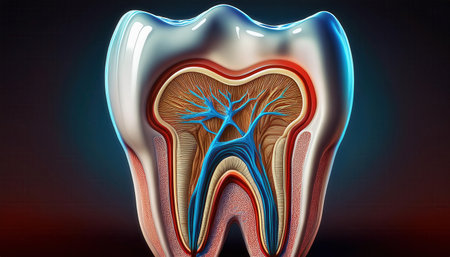

A close-up view of an anatomical model of a human molar tooth's cross-section. The white enamel cap transitions to yellow dentin, revealing the red pulp chamber and root canals within. The surrounding bone structure is depicted with porous texture in beige and red hues. The background is a solid, deep blue.

Detailed depiction of a tooths anatomy highlighting its internal structure and layers.

Tooth model displaying its complex internal structure including enamel, dentin, pulp, and root canals, standing against a vibrant background of colorful, out of focus lights

Dental tooth cross section model showing enamel, dentin, pulp, gum and root structures against a soft colorful bokeh background for oral health education and dentistry study

A detailed dental model illustrates the anatomy of a human tooth highlighting its inner structure including roots and nerves. This model is used for educational purposes in a dental clinic.

Anatomical intricacy: tooth structure, nerve, with a visible cartilaginous stage, detailed layers and components of a tooth, emphasizing the complex interplay of dental anatomy

This image provides a detailed cross-section view of a human tooth, revealing the inner anatomy including the root pulp and surrounding bone structures. It is an educational and informative visual aid

Detailed cross-section of a human tooth displaying enamel, dentin, pulp, and root anatomy. Educational medical illustration on a gradient blue background.